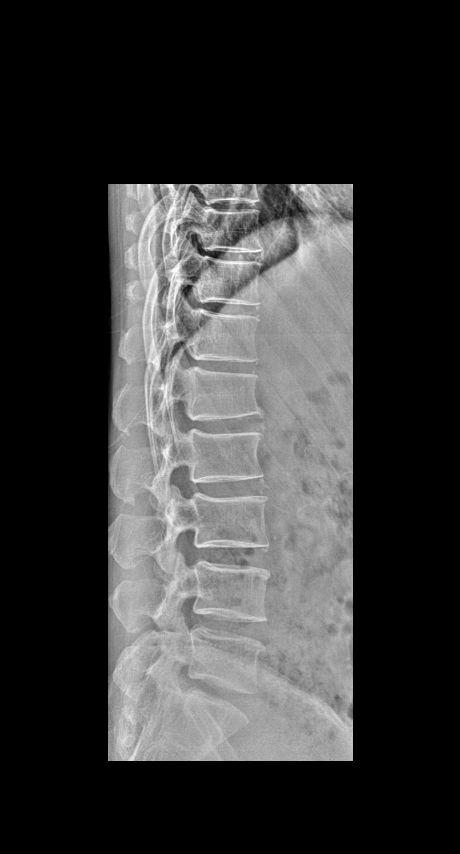

男 45 腰椎疼痛